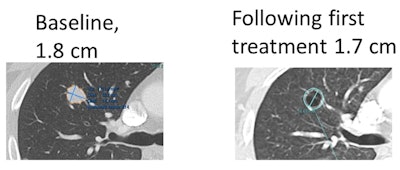

It's now accepted that 2D axial-only measurements do not accurately represent 3D tumors, Folio said. As demonstrated on their PACS (Carestream Health), current PACS tools can directly measure tumor volumes, which is an inherently more valid approach, he said.

Folio noted that a decrease in tumor density due to necrosis shown on contrast-enhanced CT can be paired with an increase in axial size despite a qualitative response to targeted treatment. Metastatic lesions often show peripheral enhancement along with nonenhancing central components, he said.

"For example, lung lesions may cavitate and measure larger on axial slices, despite showing less volume of tissue, with live tumor remaining only in the peripheral rim," he said. "The manifestation of response is reflected in decreased density [that] is incompletely captured in RECIST, which gives us the opportunity to develop more appropriate criteria and tools for this general type of therapeutic response."